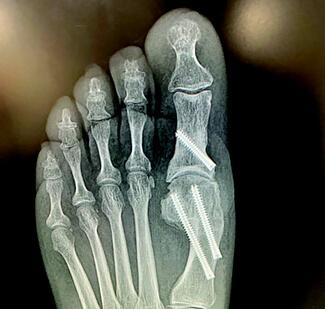

This report presents the unique perspective of a podiatric physician integrated into the surgical management of an unstable ankle fracture, performed by an orthopedic trauma surgeon. The experience highlights both the technical nuances of...